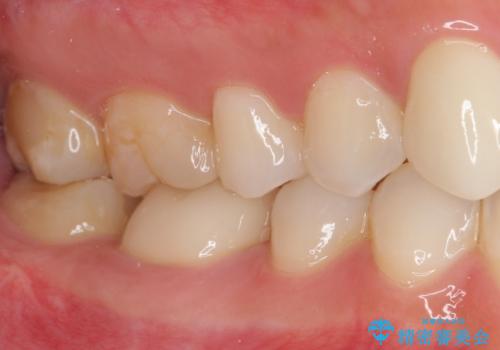

- 審美的ではない上の前歯とデコボコの下の前歯、歯茎が腫れている奥歯を気にして来院された患者様です。

根管治療の必要な歯がいくつかあるため、まずは根管治療を行い、その後インビザラインにて矯正治療を行うこととしました。

矯正治療後に前歯をセラミックブリッジに、奥の銀歯はセラミックインレーやPGAインレー(ゴールドインレー)にて補綴・修復治療を行うこととしました。

矯正治療により下顎前歯を整列させたため、上顎前歯のセラミックブリッジを補綴することで口元を少し下げることができました。

ヒトの目線がいつも口元に向けられているように感じることがなくなり、患者様には大変満足していただきました。